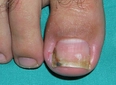

Ayak parmağı uyuşması, birçok insanın zaman zaman deneyimlediği bir durumdur. Genellikle geçici bir rahatsızlık olarak kabul edilse de, bazı durumlarda altta yatan ciddi sağlık sorunlarının belirtisi olabilir. Bu makalede, ayak parmağı uyuşmasının belirtileri, olası nedenleri ve tedavi yöntemleri ele alınacaktır. Ayak Parmağı Uyuşmasının BelirtileriAyak parmağı uyuşması, çeşitli belirtilerle kendini gösterebilir. Bu belirtiler arasında:

Bu belirtiler, genellikle geçici olmakla birlikte, bazen uzun süreli rahatsızlıklara dönüşebilir. Eğer bu belirtiler sürekli hale gelirse, bir uzmana danışmak önemlidir. Ayak Parmağı Uyuşmasının Olası NedenleriAyak parmağı uyuşmasının birçok olası nedeni bulunmaktadır. Bunlar arasında: